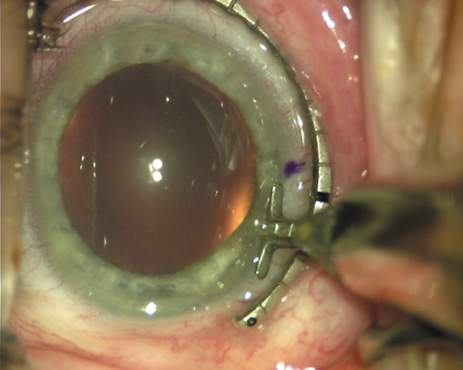

Case 1 is a 68-year-old male who presented for right cataract surgery. His refraction was −1.00 +2.25 × 80 and was recorded as reliable, consistent with his modest cataract density. Keratometry readings were 44.75 × 75 and 43.00 × 165. Corneal topography confirmed slightly more than 2.00 D of regular and slightly oblique cylinder. Consulting the nomogram, a plan was devised for a pair of LRIs to be centered over the 75-degree axis, with each incision delineating 45 degrees of arc. A single plane phaco incision was used and maintained at a size of less than 3.2 mm (Figs. 811).

Fig. 8. Steep meridian is confirmed intraoperatively by keratoscopy. In this left eye viewed from the temporal side, the “short axis” of the corneal mire is seen to be at the 75-degree meridian. (Reprinted from Hardten DR, Lindstrom RL, Davis EA. Phakic Intraocular Lenses: Principles and Practice. Thorofare, NJ: SLACK Incorporated, 2004, with permission.)

Fig. 9. The broad hash marks of the fixation ring/gauge are centered over the 75-degree meridian, using the 6:00 limbal mark for orientation. Alternatively, a Mendez gauge may be used. (Reprinted from Hardten DR, Lindstrom RL, Davis EA. Phakic Intraocular Lenses: Principles and Practice. Thorofare, NJ: SLACK Incorporated, 2004, with permission.)

Fig. 10. The single footplate diamond blade is inserted perpendicular to the corneal surface and at the peripheral most extent of clear corneal tissue. In this case, the nomogram calls for arcuate incisions of 45 degrees. Therefore, the incision is begun approximately 22.5 degrees to one side of the broad hash mark. (Reprinted from Hardten DR, Lindstrom RL, Davis EA. Phakic Intraocular Lenses: Principles and Practice. Thorofare, NJ: SLACK Incorporated, 2004, with permission.)

Fig. 11. Opposite relaxing incision is completed. (Reprinted from Hardten DR, Lindstrom RL, Davis EA. Phakic Intraocular Lenses: Principles and Practice. Thorofare, NJ: SLACK Incorporated, 2004, with permission.)